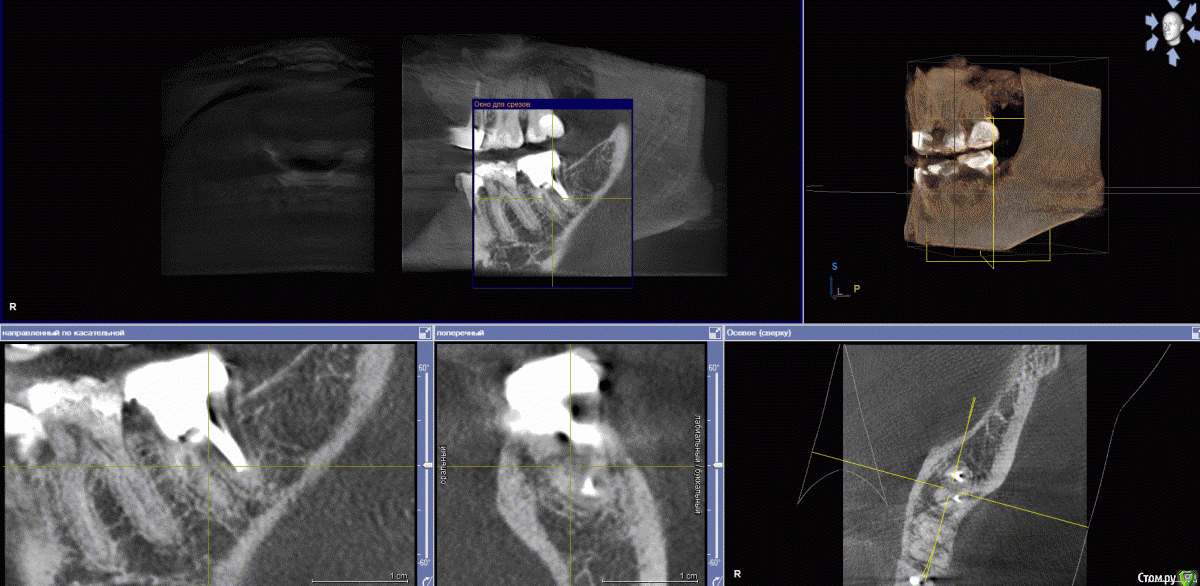

Jaz Опубликовано 23 сентября, 2017 Поделиться Опубликовано 23 сентября, 2017 (изменено) Здравствуйте!Итак, имеется в наличии зуб 47 (или 37? в общем, нижняя левая семерка). Года три как депульпирован, установлена вкладка и металлокерамика (материалы не знаю). По КТ нашли кариес под коронкой и кариес корня, т.е. 100% удаление.Жевательных зубов у меня и так прискорбно мало. Хочу ставить имплант. Но начиталась таких ужасов про имплантацию, что хотела бы собрать мнения знающих людей, прежде чем начинать сию операцию. совершенно запуталась в обилии информации. 1) одномоментная или классическая? Зуб еще на месте, и, как я поняла, лучше ставить имплант сразу после того, как зуб выдерут? Никаких заболеваний у меня вроде нет (но может нужно какие анализы сдать и провериться? на диабет меня не проверяли просто)2) нужна ли в моем случае подсадка кости или какие-то иные манипуляции, требующие затрат (планирую брать кредит, момент важный)3) у меня глубины и ширины кости вообще для имплантации хватает? или мне морально готовиться к вставной челюсти в 30 лет?3) прочитала здесь на форуме, что на нижние семерки сразу нагрузку не дают. Но разве это не приведет к деградации кости?4) какой производитель все же лучше? Насчет коронки, как я понимаю, лучше цирконий? Я работаю с химикатами (формалин, ксилолы, фиксаторы и вся прочая патологоанотомическая каша) - есть в этом случае какие-то нюансы в выборе материала для штифта и коронки? Прилагаю снимки КТ. Толком не поняла, как их в программе делать. Если что - переделаю. Изменено 23 сентября, 2017 пользователем Jaz Ссылка на комментарий

колесников Опубликовано 23 сентября, 2017 Поделиться Опубликовано 23 сентября, 2017 (изменено) Здравствуйте! В вашем случае предпочтение к одномоментной имплантации. (Костной ткани достаточно для первичной стабильности импланта,но есть тенденция к образованию узкого гребня после удаления). Из дополнительных расходов будет:удаление зуба,0.5 г кости,возможно пересадка лоскута десны,установка формирователя десны.Систему лучше выбирать совместно с вашим доктором. Изменено 23 сентября, 2017 пользователем колесников Ссылка на комментарий